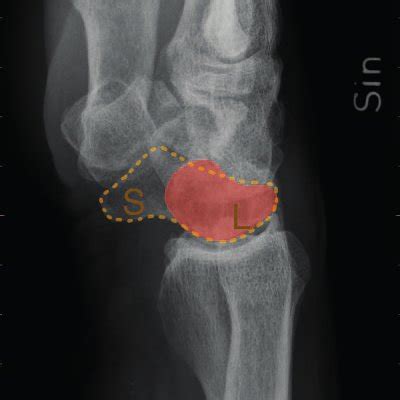

Radiographic Findings Consistent with DISI (Dorsal Intercalated Segment Instability) edit

DISI is a pattern of carpal instability in which the lunate tilts dorsally (extends) on the lateral wrist radiograph. It occurs most commonly after Scapholunate ligament injury. Mechanism in brief:

• Scaphoid loses its stabilizing link to the lunate → scaphoid collapses into flexion

• Lunate, pulled by the triquetrum and capitate, rotates into extension (dorsiflexion)

2) Key Radiographic Findings (High-yield for exams) edit

A) Lateral view (the most important view) edit

The diagnosis of DISI is primarily made on a true lateral wrist radiograph.

1. Increased Scapholunate Angle (SLA)

• Normal: approximately 30°–60°

• DISI: typically greater than 70°

• This is the single most quoted numeric criterion in exams

1. Increased Radiolunate Angle (RLA)

• Normal: near neutral

• DISI: greater than 10°, reflecting dorsal lunate tilt

1. Increased Capitolunate (Lunocapitate) Angle

• Normal: less than 30°

• DISI: greater than 30°, indicating loss of collinearity between lunate and capitate

1. Scapholunate gap widening

• Increased distance between scaphoid and lunate

• Known as the “Terry Thomas sign”